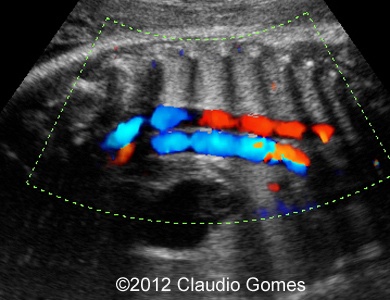

Images 8-11: Persistent right umbilical vein and Inferior vena cava interruption with continuity of the flow via Azygos vein on grayscale and color Doppler

Fig8

Fig9

Fig10

Fig11